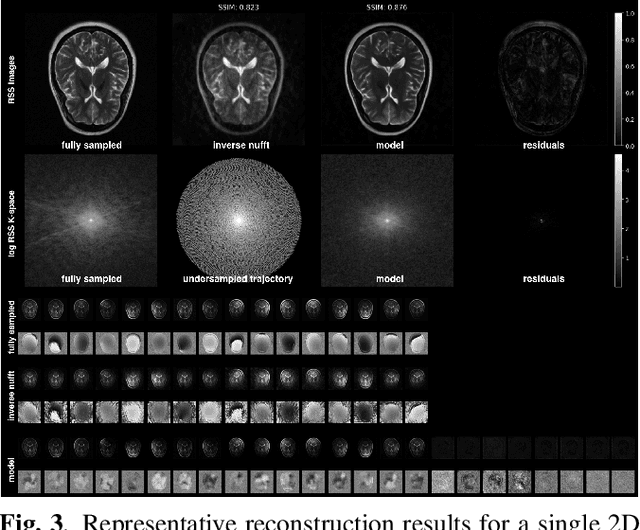

Abstract:Deep learning methods for accelerated MRI achieve state-of-the-art results but largely ignore additional speedups possible with noncartesian sampling trajectories. To address this gap, we created a generative diffusion model-based reconstruction algorithm for multi-coil highly undersampled spiral MRI. This model uses conditioning during training as well as frequency-based guidance to ensure consistency between images and measurements. Evaluated on retrospective data, we show high quality (structural similarity > 0.87) in reconstructed images with ultrafast scan times (0.02 seconds for a 2D image). We use this algorithm to identify a set of optimal variable-density spiral trajectories and show large improvements in image quality compared to conventional reconstruction using the non-uniform fast Fourier transform. By combining efficient spiral sampling trajectories, multicoil imaging, and deep learning reconstruction, these methods could enable the extremely high acceleration factors needed for real-time 3D imaging.